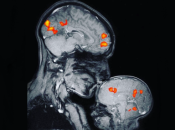

Команда исследователей из Принстона провела первое исследование того, как мозг ребенка и взрослого взаимодействуют во время игры, они обнаружили сходство в их нервной деятельности и похожую активность мозга в одних и тех же областях.

Другими словами, активность мозга ребенка и взрослого росла и падала вместе, когда они играли вместе, или был зрительный контакт.

Анализ полученных данных показал, что во время общения лицом к лицу мозг малыша начинает работать в унисон с мозгом взрослого.

Когда взрослый и младенец отворачивались друг от друга и общались с другими людьми, связь между ними исчезла.

При этом раньше других начинают подстраиваться те отделы мозга ребенка, которые вовлечены в процесс понимания окружающего мира.

Сильнее остальных областей мозга в работу включается префронтальная кора, которая отвечает за мышление, планирование, самоконтроль и обучение.